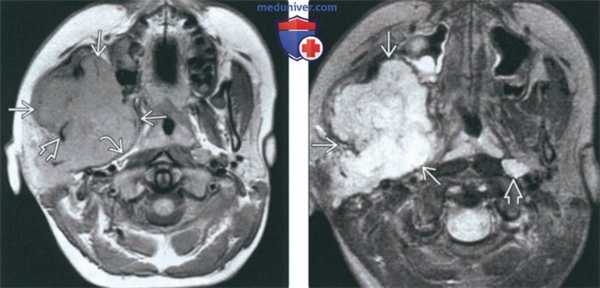

(Слева) На аксиальной МРТ (Т1ВИ) в жевательном пространстве визуализируется саркома Юинга в виде огромного объемного образования с гиперинтенсивным относительно мышц сигналом. Ветвь нижней челюсти разрушена, на этом изображении виден лишь ее мелкий фрагмент. Полоска окологлоточного жира смещена кнутри.

(Справа) На аксиальной МРТ (Т2ВИ FS) у этого же пациента определяется неоднородный сигнал крайне высокой интенсивности в опухоли. Хорошо различимый заглоточный лимфоузел слева является случайной находкой.г) Патология:

(Слева) МРТ Т1ВИ в аксиальной проекции. Саркома Юинга, локализующаяся в жевательном пространстве. Обратите внимание, что сигнал относительно здоровых мышц гиперинтенсивный. Нижняя челюсть разрушена, определяется лишь небольшой ее фрагмент. Жировая клетчатка окологлоточного пространства смещена в медиальную сторону.

(Справа) МРТ Т2ВИ FS, аксиальная проекция, тот же пациент. Неоднородный сигнал высокой интенсивности. Крупный лимфоузел в заглоточном пространстве слева представляет собой случайную находку.1. Общая характеристика: